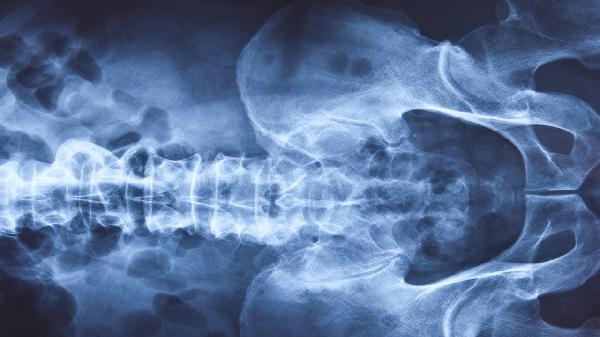

TCT检查提示轻度炎症合并HPV阳性可通过定期复查、增强免疫力、局部药物治疗、物理治疗等方式干预。HPV感染多由性接触传播、免疫力低下、黏膜损伤、高危型病毒持续感染等因素引起。

1、定期复查

每6-12个月重复TCT及HPV检测,监测病毒载量和宫颈细胞变化。30岁以上建议联合阴道镜检查,排除宫颈上皮内瘤变。